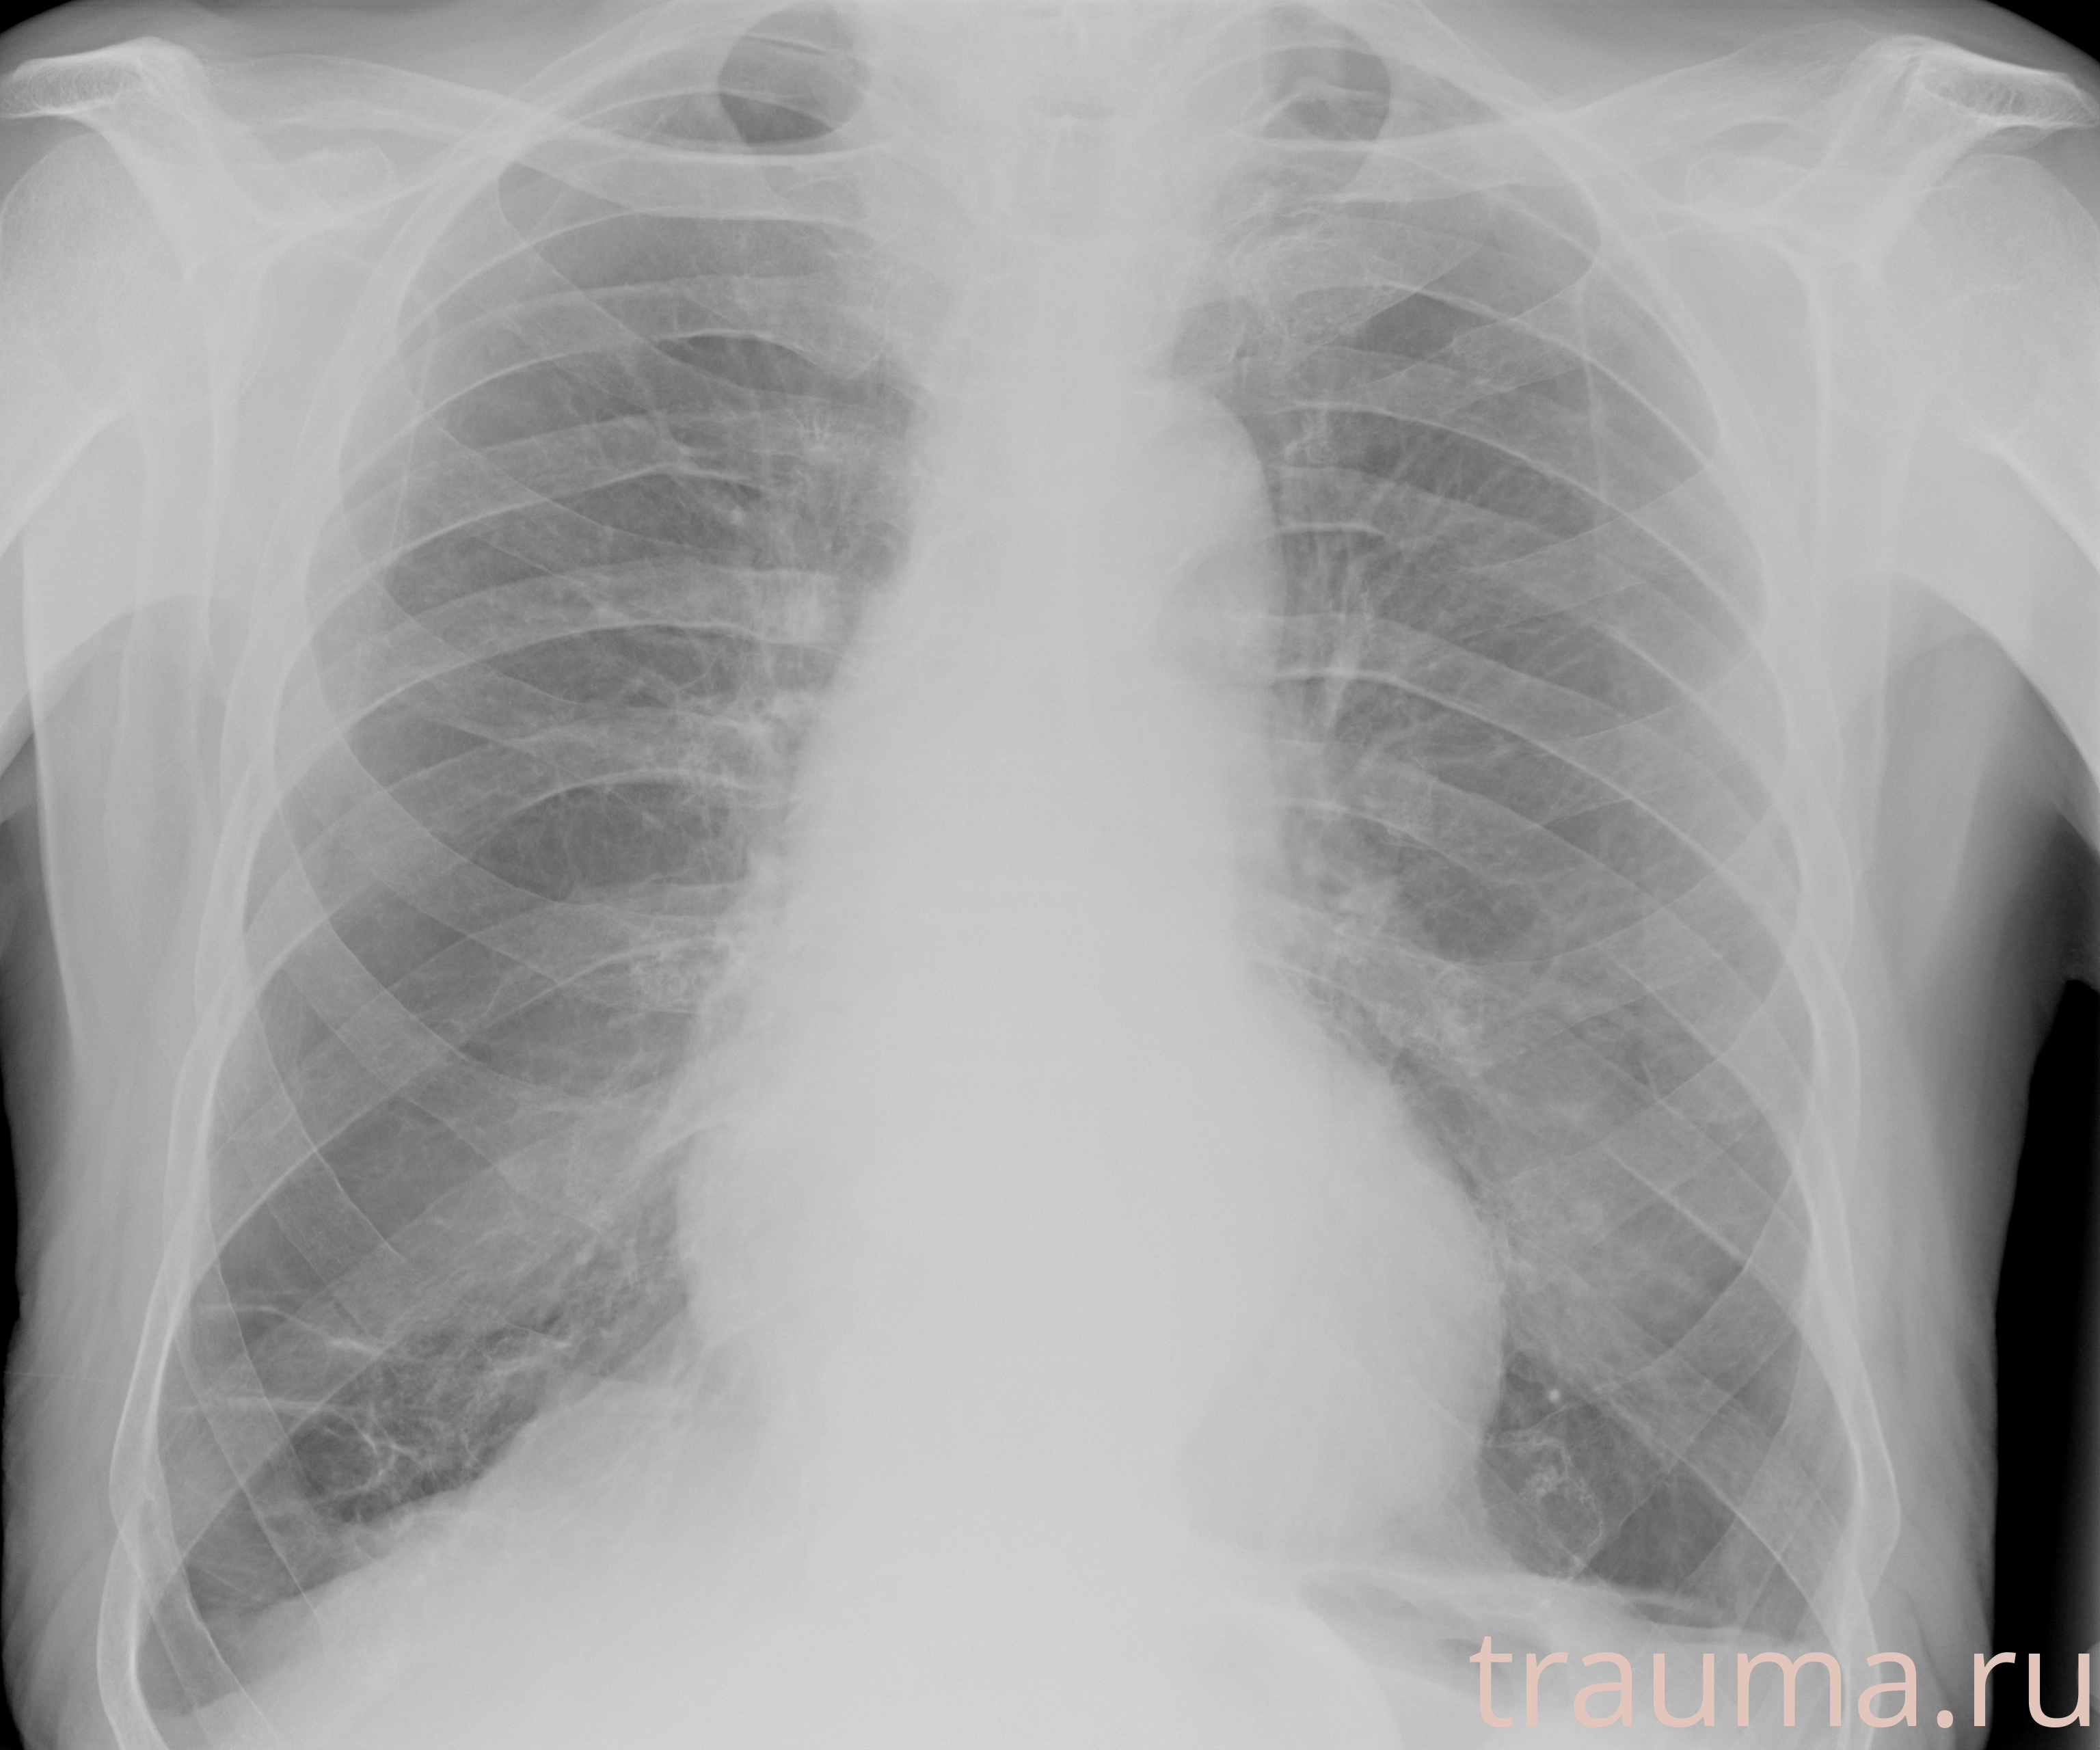

Рентген на дому: по вашему адресу приезжает врач-рентгенолог, травматолог-ортопед с мобильным рентгеновским аппаратом, проводит диагностику травмы или заболевания, делает необходимые рентгенограммы, дает рекомендации по дальнейшему лечению. Получить качественные снимки в домашних условиях возможно благодаря уникальной методике, разработанной МосРентген Центром для института  Склифосовского

при переломе шейки бедра и пневмонии от компании МосРентген Центр - партнера Института имени Склифосовского